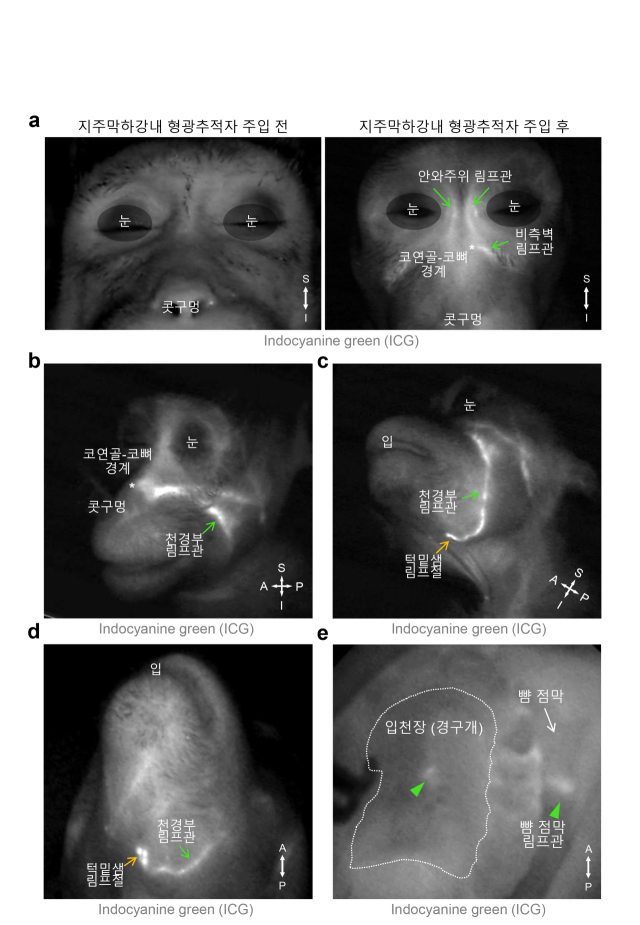

연구팀은 림프관에 선택적으로 형광 표지자를 발현하는 생쥐 모델과 생체 내 이미징 기술 등 첨단 시각화 기술을 활용해 뇌척수액 배출경로를 시각화했다.

그 결과, 뇌척수액이 눈 주위, 코안 쪽 그리고 입천장의 림프관을 통해 얼굴 피부 아래 림프관으로 모인 뒤 턱밑샘 림프절로 배출됨을 규명했다.